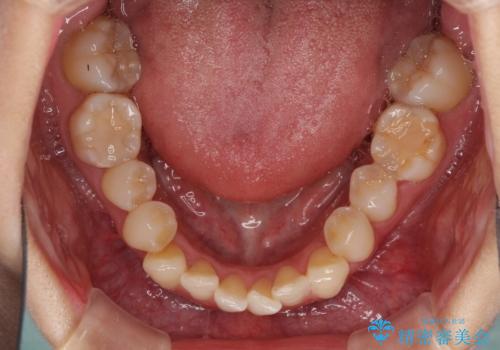

- 奥歯の咬み合わせを気にして来院された患者様です。

上顎骨の幅が下顎骨よりも小さいので、拡大装置により骨幅を広げて上下関係を改善し、その後インビザラインにて歯並びを整えることとしました。

上下の骨幅を改善したことで、スムーズに歯列矯正を行うことができました。

奥歯の咬み合わせを改善する必要があったため、治療は長期化しましたが、きっちりと仕上げることができました。